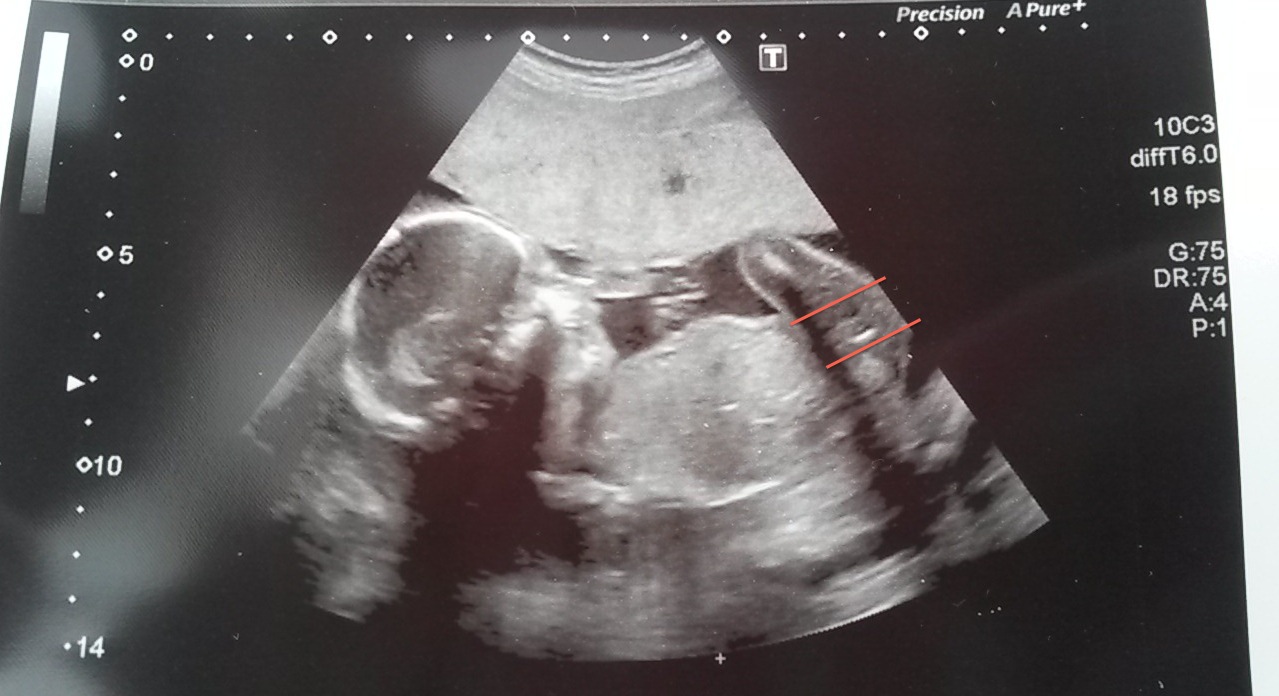

torturing myself after 20 week scan